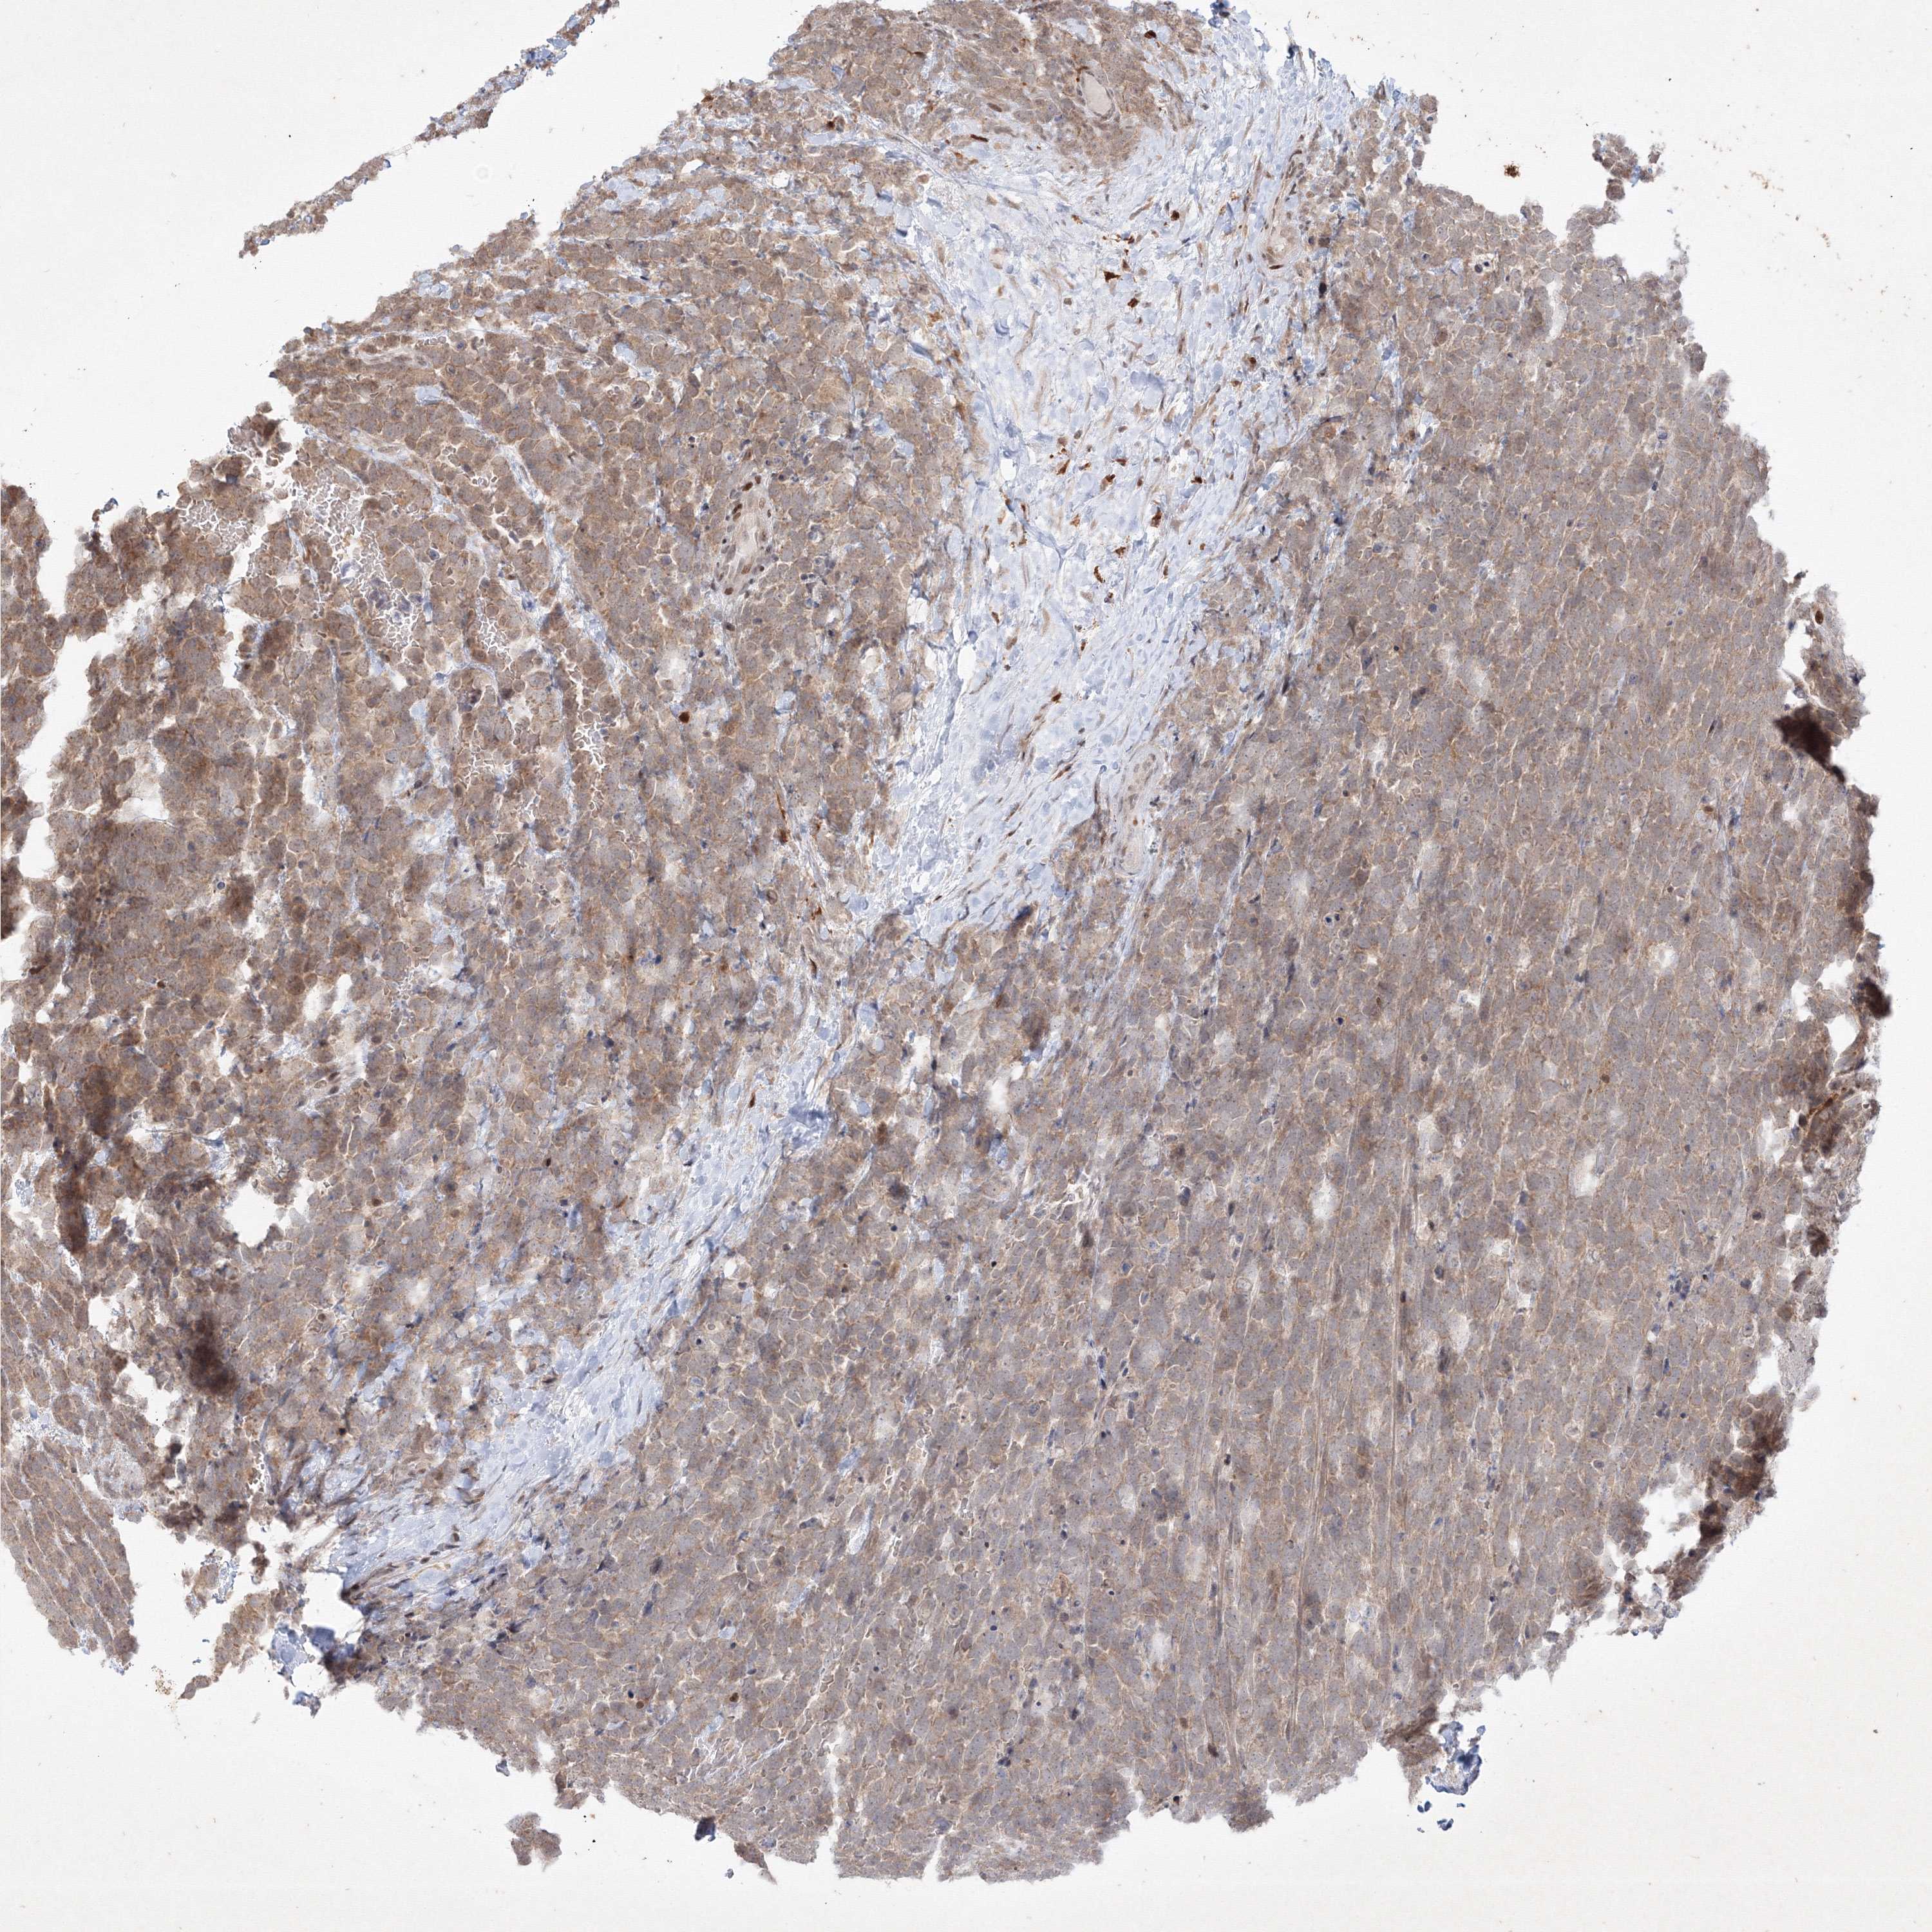

UROTHELIAL CANCER - Protein expressioni

A mouse-over function shows sample information and annotation data. Click on an image to view it in a full screen mode. Samples can be filtered based on level of antibody staining by selecting one or several of the following categories: high, medium, low and not detected. The assay and annotation is described here.

Note that samples used for immunohistochemistry by the Human Protein Atlas do not correspond to samples in the TCGA dataset.

Antibody stainingi

Antibody staining in the annotated cell types in the current human tissue is reported as not detected, low, medium, or high, based on conventional immunohistochemistry profiling in selected tissues. This score is based on the combination of the staining intensity and fraction of stained cells.

Each image is clickable and will lead to virtual microscopy that enables deeper exploration of all samples and also displays staining intensity scores, fraction scores and subcellular localization as well as patient and tissue information for each sample.

Antibody HPA039988

Antibody HPA057104

Antibody CAB032328

Staining

High

Medium

Low

Not detected

Intensity

Strong

Moderate

Weak

Negative

Quantity

>75%

75%-25%

<25%

None

Location

Nuclear

Cytoplasmic/membranous

Cytoplasmic/membranous,nuclear

Urothelial carcinoma, Low grade

Urothelial carcinoma, High grade